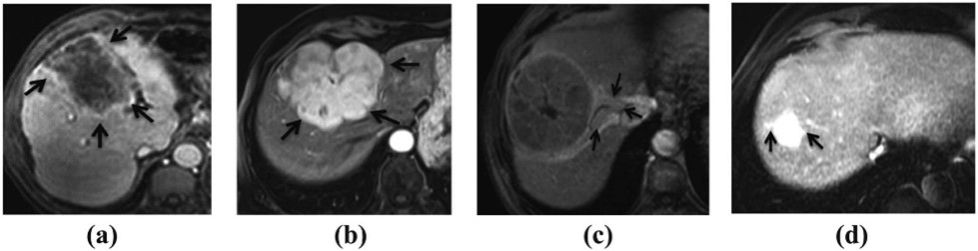

原发性肝癌是主要的全球健康威胁之一,在最常见和最致命的恶性肿瘤中排名第六。肝癌早期症状一般较为隐匿,不易被察觉,大约70%的肝癌病例只有在中期或晚期才能够被诊断出来。尽管外科和内科治疗都有一定效果,但肝癌患者的5年生存率仍低于30%。虽然肝切除术是早期肝癌的关键治疗方法,但是术后肿瘤复发率仍然较高。微血管侵犯(MVI)是微血管中存在的癌性血栓(如图1所示),肉眼无法检测到,但在显微镜下可识别。MVI可独立预测肝癌切除术后早期复发及预后不良,准确的术前MVI评估对于指导肝癌患者的治疗决策和提高生存率至关重要。

图1: MVI发生时器官产生的不同表现:(a)肿瘤包膜的外观、(b)肿瘤边缘、(c)瘤周异常增强和(d)外周动脉增强。